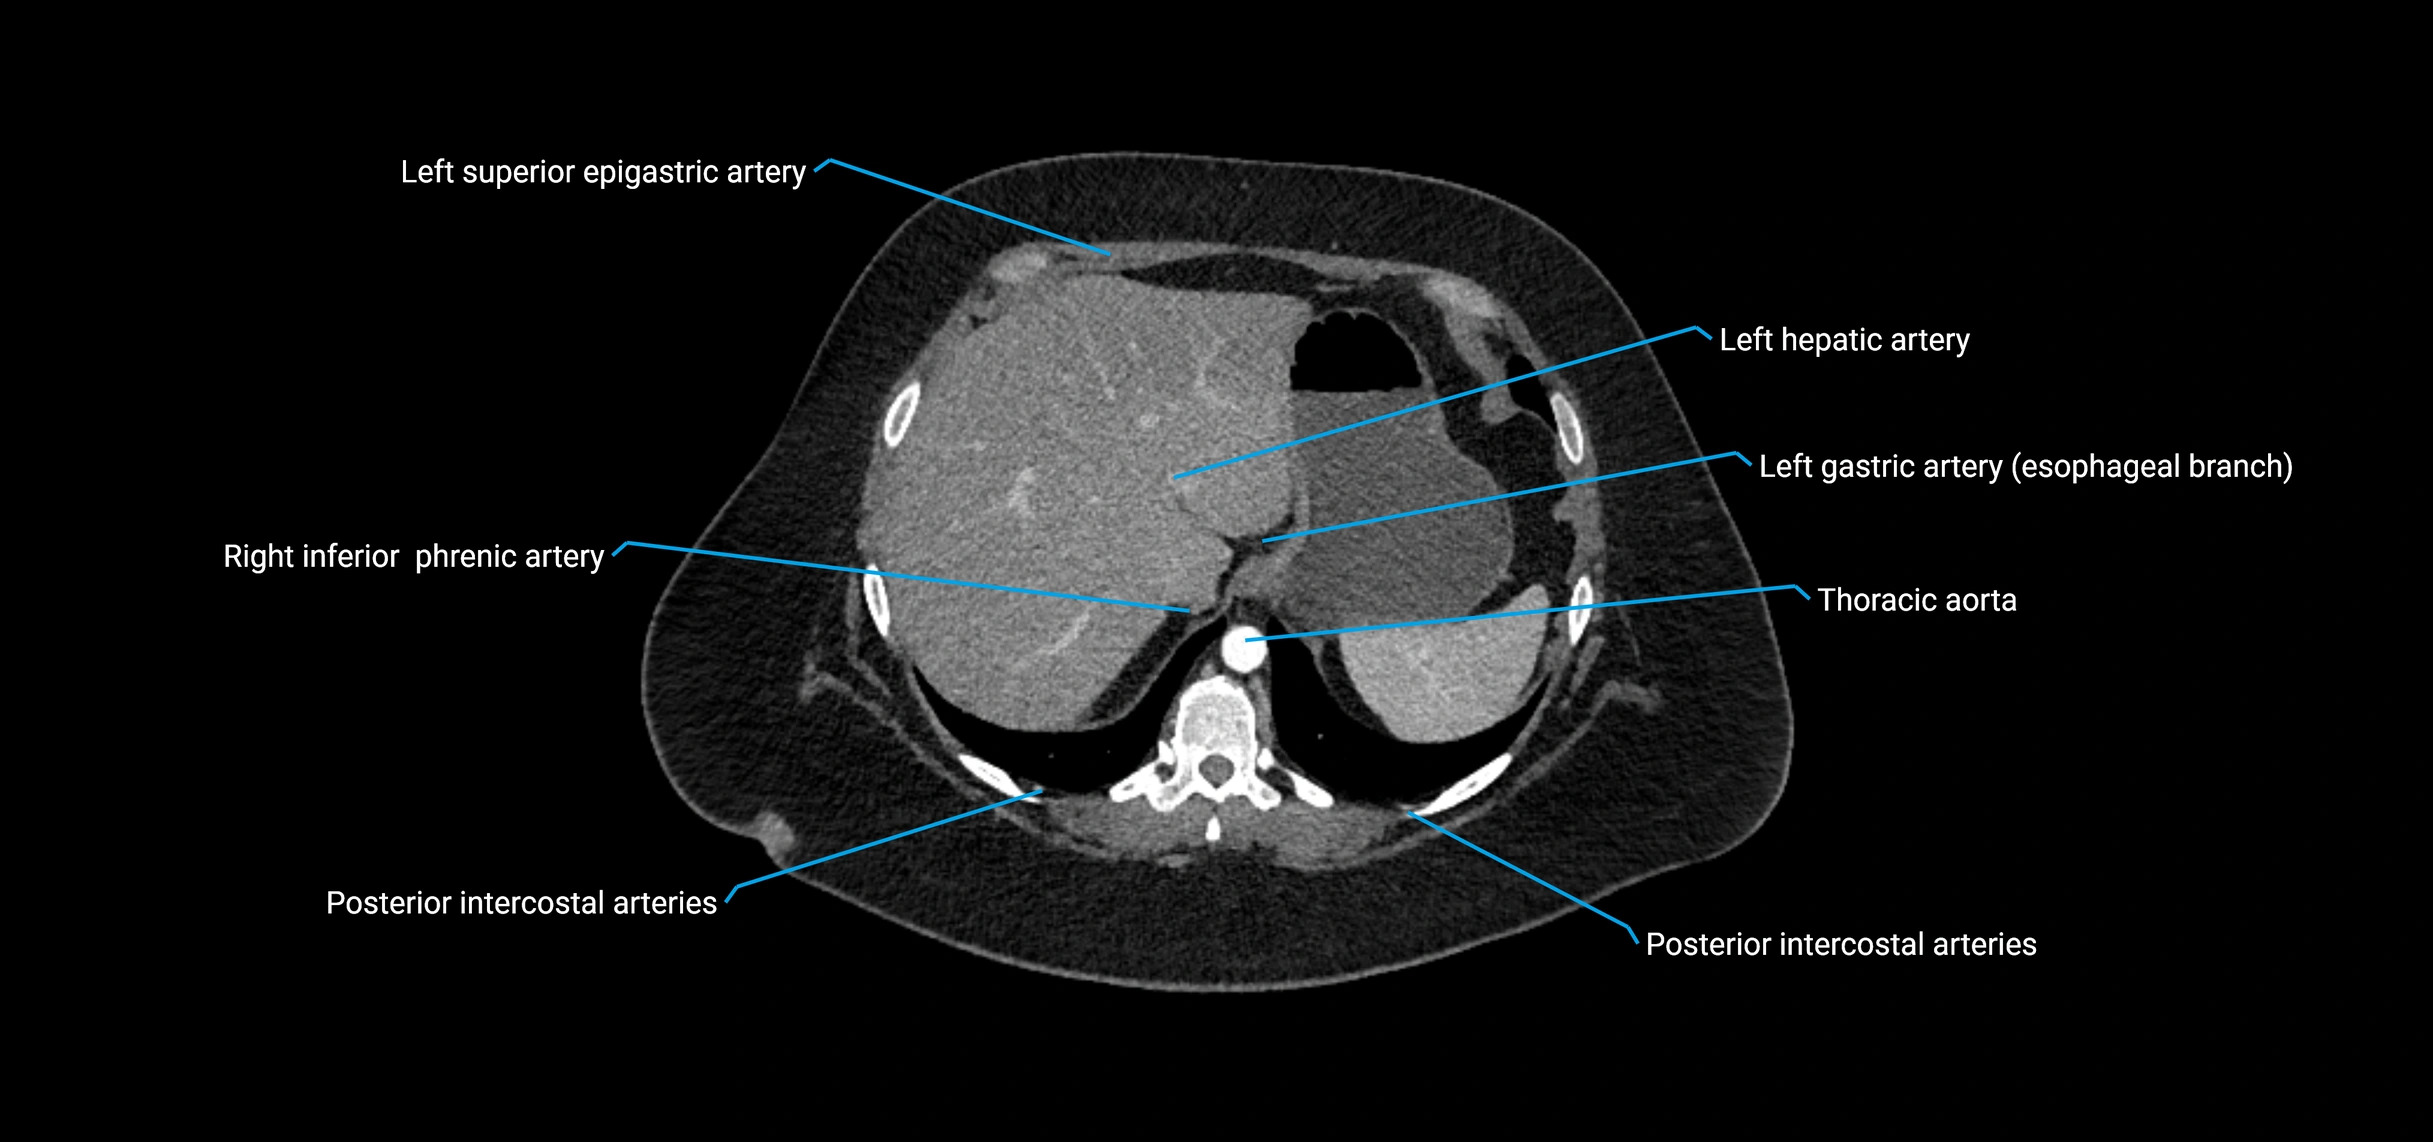

The abdominal aorta is the continuation of the thoracic aorta, beginning at the level of the aortic hiatus of the diaphragm (T12 vertebra) and terminating at the level of the L4 vertebra where it bifurcates into the right and left common iliac arteries. It lies slightly to the left of the midline and courses anterior to the vertebral bodies, surrounded by the retroperitoneal structures of the abdomen.

The abdominal aorta gives off numerous visceral and parietal branches, supplying the abdominal organs, pelvic structures, and lower limbs. It is the main conduit of oxygenated blood from the heart to the abdomen and lower body. The aorta is clinically significant as the common site of aneurysm, dissection, atherosclerosis, and traumatic injury.

CT Appearance

Non-contrast CT:

• Appears as a tubular soft tissue structure anterior to vertebral bodies

• Calcified atherosclerotic plaques appear as hyperdense foci along the wall

• Useful for screening abdominal aortic aneurysm (AAA) size and mural calcification

Contrast-enhanced CT (CTA):

• Gold standard for abdominal aortic imaging

• Provides excellent detail of lumen, wall, aneurysm, thrombus, and branch vessels

• Multiplanar and 3D reconstructions help in aneurysm measurement, stent graft planning, and dissection evaluation

• Detects acute rupture, traumatic injury, or occlusion with high sensitivity